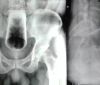

Homem fica com copo preso no ânus durante três dias e passa por cirurgia